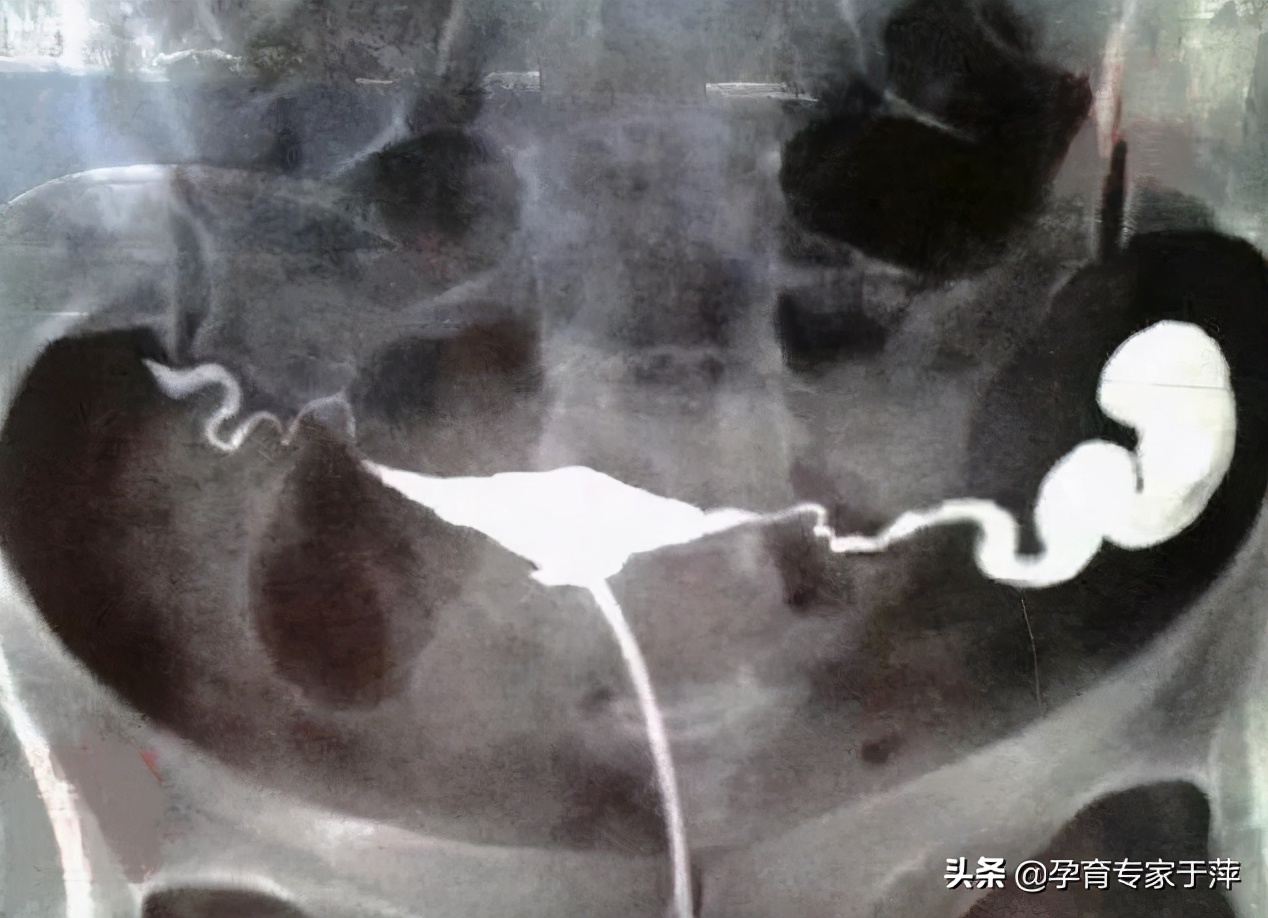

问:子宫输卵管造影提示“输卵管粘连”,我想自然受孕,可以手术治疗输卵管吗?

答:“输卵管粘连”是通过影像学检查对输卵管通畅程度的描述。粘连的表现及程度也各有不同。对于输卵管粘连导致的不孕可以首先考虑中医口服、灌肠、外敷三联法保守治疗,如保守治疗无效,再可以考虑手术。